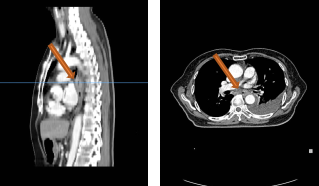

胸部平扫+增强CT(2020-08-27):食道中段管壁增厚,上下累及约4.5厘米(约胸5/6椎间隙水平至胸8椎体上缘水平),增强后可见轻度强化,隆突下见境界不清淋巴结。左肺上叶尖后段及相邻左肺下叶背段交界处见团块状直径约2.5厘米软组织密度灶,边缘可见毛刺,左侧胸腔积液,左下肺膨胀不全。右肺下叶见少许条状影。结论:1、食管癌。2、左肺上叶尖后段病灶,符合肺癌。左侧胸腔积液,左下肺膨胀不全。

GTVp1为食管肿瘤,GTVp2为肺肿瘤。

分割方式:

95%PGTVp1:60Gy/2Gy/30F;

95%PGTVp2:60Gy/2Gy/30F;

后肺原发灶补量照射:95%PGTVp2:8Gy/2Gy/4F。

放疗同期行同步化疗+靶向治疗,具体方案为:洛铂50mg d1 q21d+尼妥珠单抗400mg Qw。放化疗前开始行重组人血管内皮抑制素(恩度)30mg d1-7q3w抗血管靶向治疗。放化疗结束后给予抗血管靶向及针对肺原发灶TKI靶向治疗维持,TKI靶向:克唑替尼250mg Bid po Qd。治疗后3个月,患者拒绝继续恩度靶向治疗。治疗后6月患者拒绝克唑替尼治疗。考虑肺癌为驱动基因阳性型,未能行食管癌治疗后免疫治疗维持。